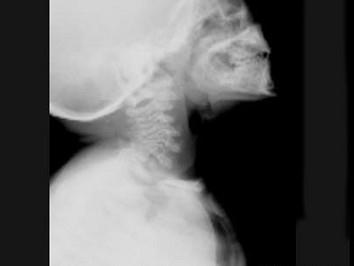

问题 女,3岁,身高不增,智力正常,请结合图像,选出最可能的诊断 ( )

选项 A、粘多糖贮积症I型 B、MPSII型 C、肾性骨病 D、粘多糖贮积症IV型 E、维生素D缺乏症

答案 D